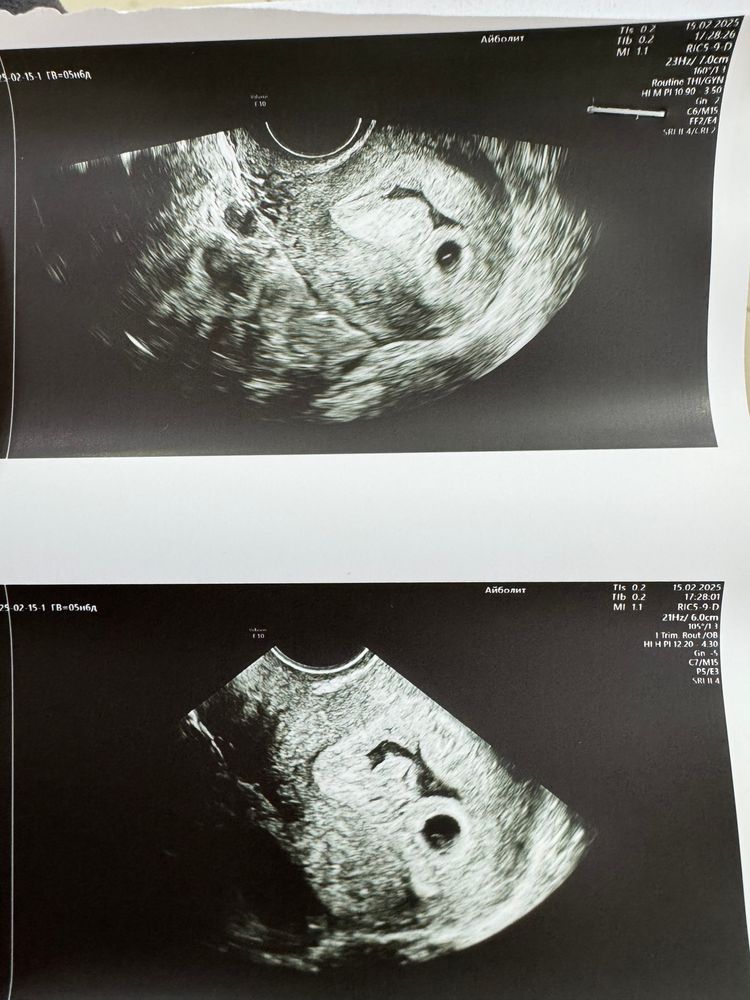

УЗИ в 5н6д и гематома

Ну что, сходила сегодня на узи, по последним месячным срок 5н6д, овуляция была на 17-18 дц. Нашли ПЯ и ЖМ, по ПЯ срок поставили 5н5д, и гематому 🤦🏻♀️ коричневых выделений не было, немного тянул низ живота. В общем без этой гематомы была бы счастлива) У кого было на таком сроке, чем закончилось? Врачу своему написала, но пока не отвечает. Смущал немного прирост ХГЧ, 17 дпо - 650, 19 дпо - 1131, 21 дпо - 1941. Сегодня на 24 дпо пришел результат 5683, все больше сдавать не буду)